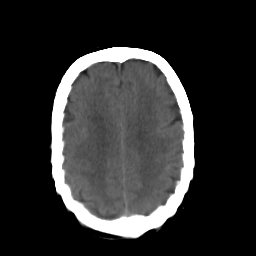

In this study, the dataset introduced in [8], which is publicly available111https://github.com/ChengBinJin/MRI-to-CT-DCNN-TensorFlow, is used for performance evaluation. It consists of 367 paired CT and MR images with the size of 512256. In the original dataset, it is noted that several CT images have stereotactic head frame that was used in Gamma Knife treatment. This head frame manually removed from the CT images. In addition, there exist various CT and MR slices that brings incredible difficulty in training the generator. Therefore, 100 images are selected from similar slices for each modality, in which 90 and 10 images are used for training and testing, respectively. Fig. 5 shows four examples of pre-processed samples.